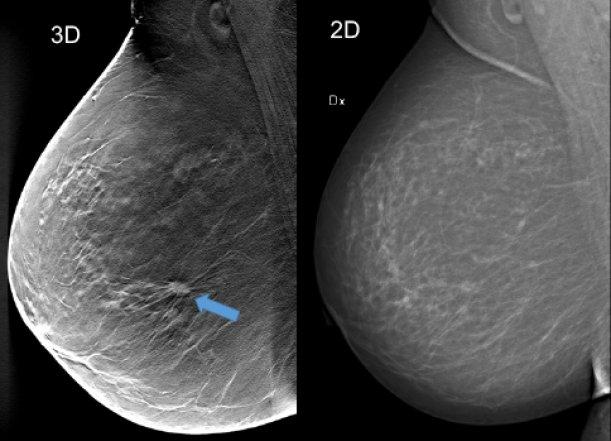

УЗИ молочных желез — информативный и безопасный метод диагностики, с помощью которого можно точно оценить состояние желез, обнаружить доброкачественные и злокачественные образования, уточнить диагноз. Это доступное по цене исследование безвредно и не несет лучевой нагрузки. Оно имеет большое значение в ранней диагностике заболеваний и нередко применяется в профилактических целях. На УЗИ может направить маммолог, онколог, эндокринолог, гинеколог.

Сделать УЗИ молочных желез можно в качестве первичной диагностики и для уточнения уже предполагаемого диагноза. Метод основывается на способности высокочастотных ультразвуковых волн с различной скоростью отражаться от тканей с разной плотностью.

С помощью ультразвуковой диагностики можно обнаружить следующие заболевания:

Для оценки кровотока в тканях молочных желез используется доплерография. Данные, полученные в результате биопсии под контролем УЗ-аппарата, могут сказать о природе и характере образований в молочных железах.

Кому противопоказано

УЗИ практически не имеет противопоказаний. Однако важно отметить, что информативность обследования груди таким способом у женщин молодого возраста выше, поскольку ткани молочных желез с возрастом становятся более рыхлыми. Поэтому после 40 лет УЗИ в большинстве случаев сочетается с рентген-диагностикой (маммографией).